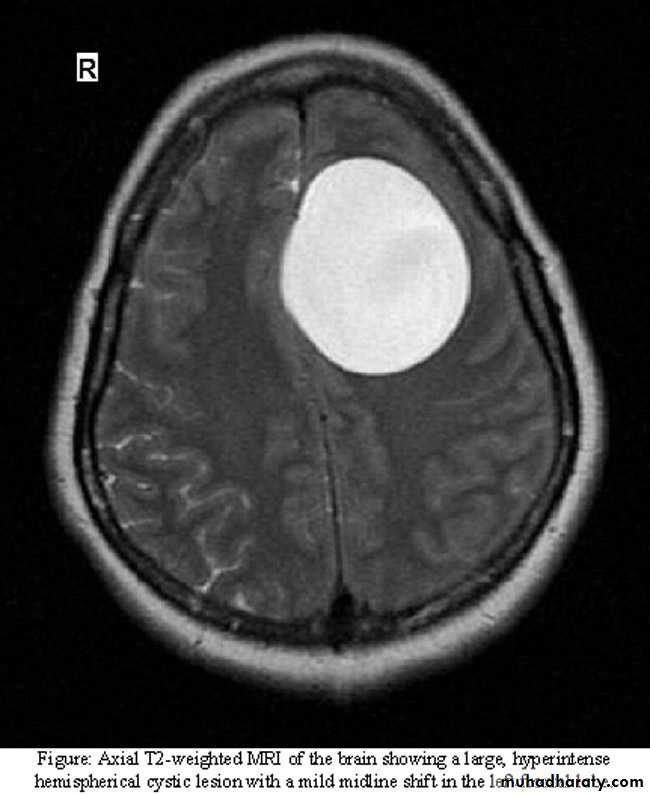

Brain MRI show. LF frontal lobe H.cyst

cestodes